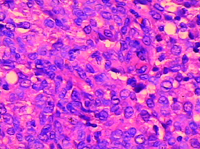

眼瞼膿腫細胞眼瞼膿腫

眼瞼膿腫多因外傷感染而起,也有繼眼眶骨膜炎和骨髓炎而起者。多見於患結核病的兒童,也可見於丹毒浸入深層時的患者。臨床上眼瞼明顯水腫充血,伴有球結膜水腫,耳前或頜下淋巴結腫大,全身反應也較顯著。晚期膿腫有波動感,最後膿液穿破皮膚排出而癒合。但偶有感染蔓延至眼眶深部而引起嚴重顱內感染者。